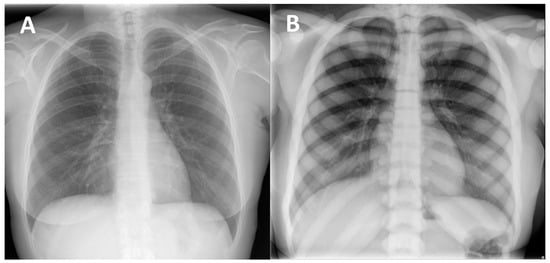

(1) Diffuse increased bone density, sclerosis involving the skull, spine, pelvis, and appendicular bones: This sign is the most known and recognized imaging feature of osteopetrosis, and the reason for the name ‘marble bone disease’ of this condition. Diffuse bone sclerosis can be found in all subtypes of osteopetrosis (ADO, ARO, IAO), even if with slightly different patterns and skeletal locations; particularly in the ARO type, the bone sclerosis can be so marked to assume the so-called ‘marble bone’ appearance (Figure 1).

Figure 1. (A) conventional radiography of the chest of a young healthy female (shown as comparison). (B) conventional radiography of the chest in a 29-year-old female diagnosed with osteopetrosis (clinical and radiological diagnosis in absence of a pathogenic variant in osteopetrosis-related genes). All the skeletal segments included are affected by diffuse and markedly increased bone density (spine, ribs, clavicle, scapulae, humerus): ‘Marble bone’ appearance.